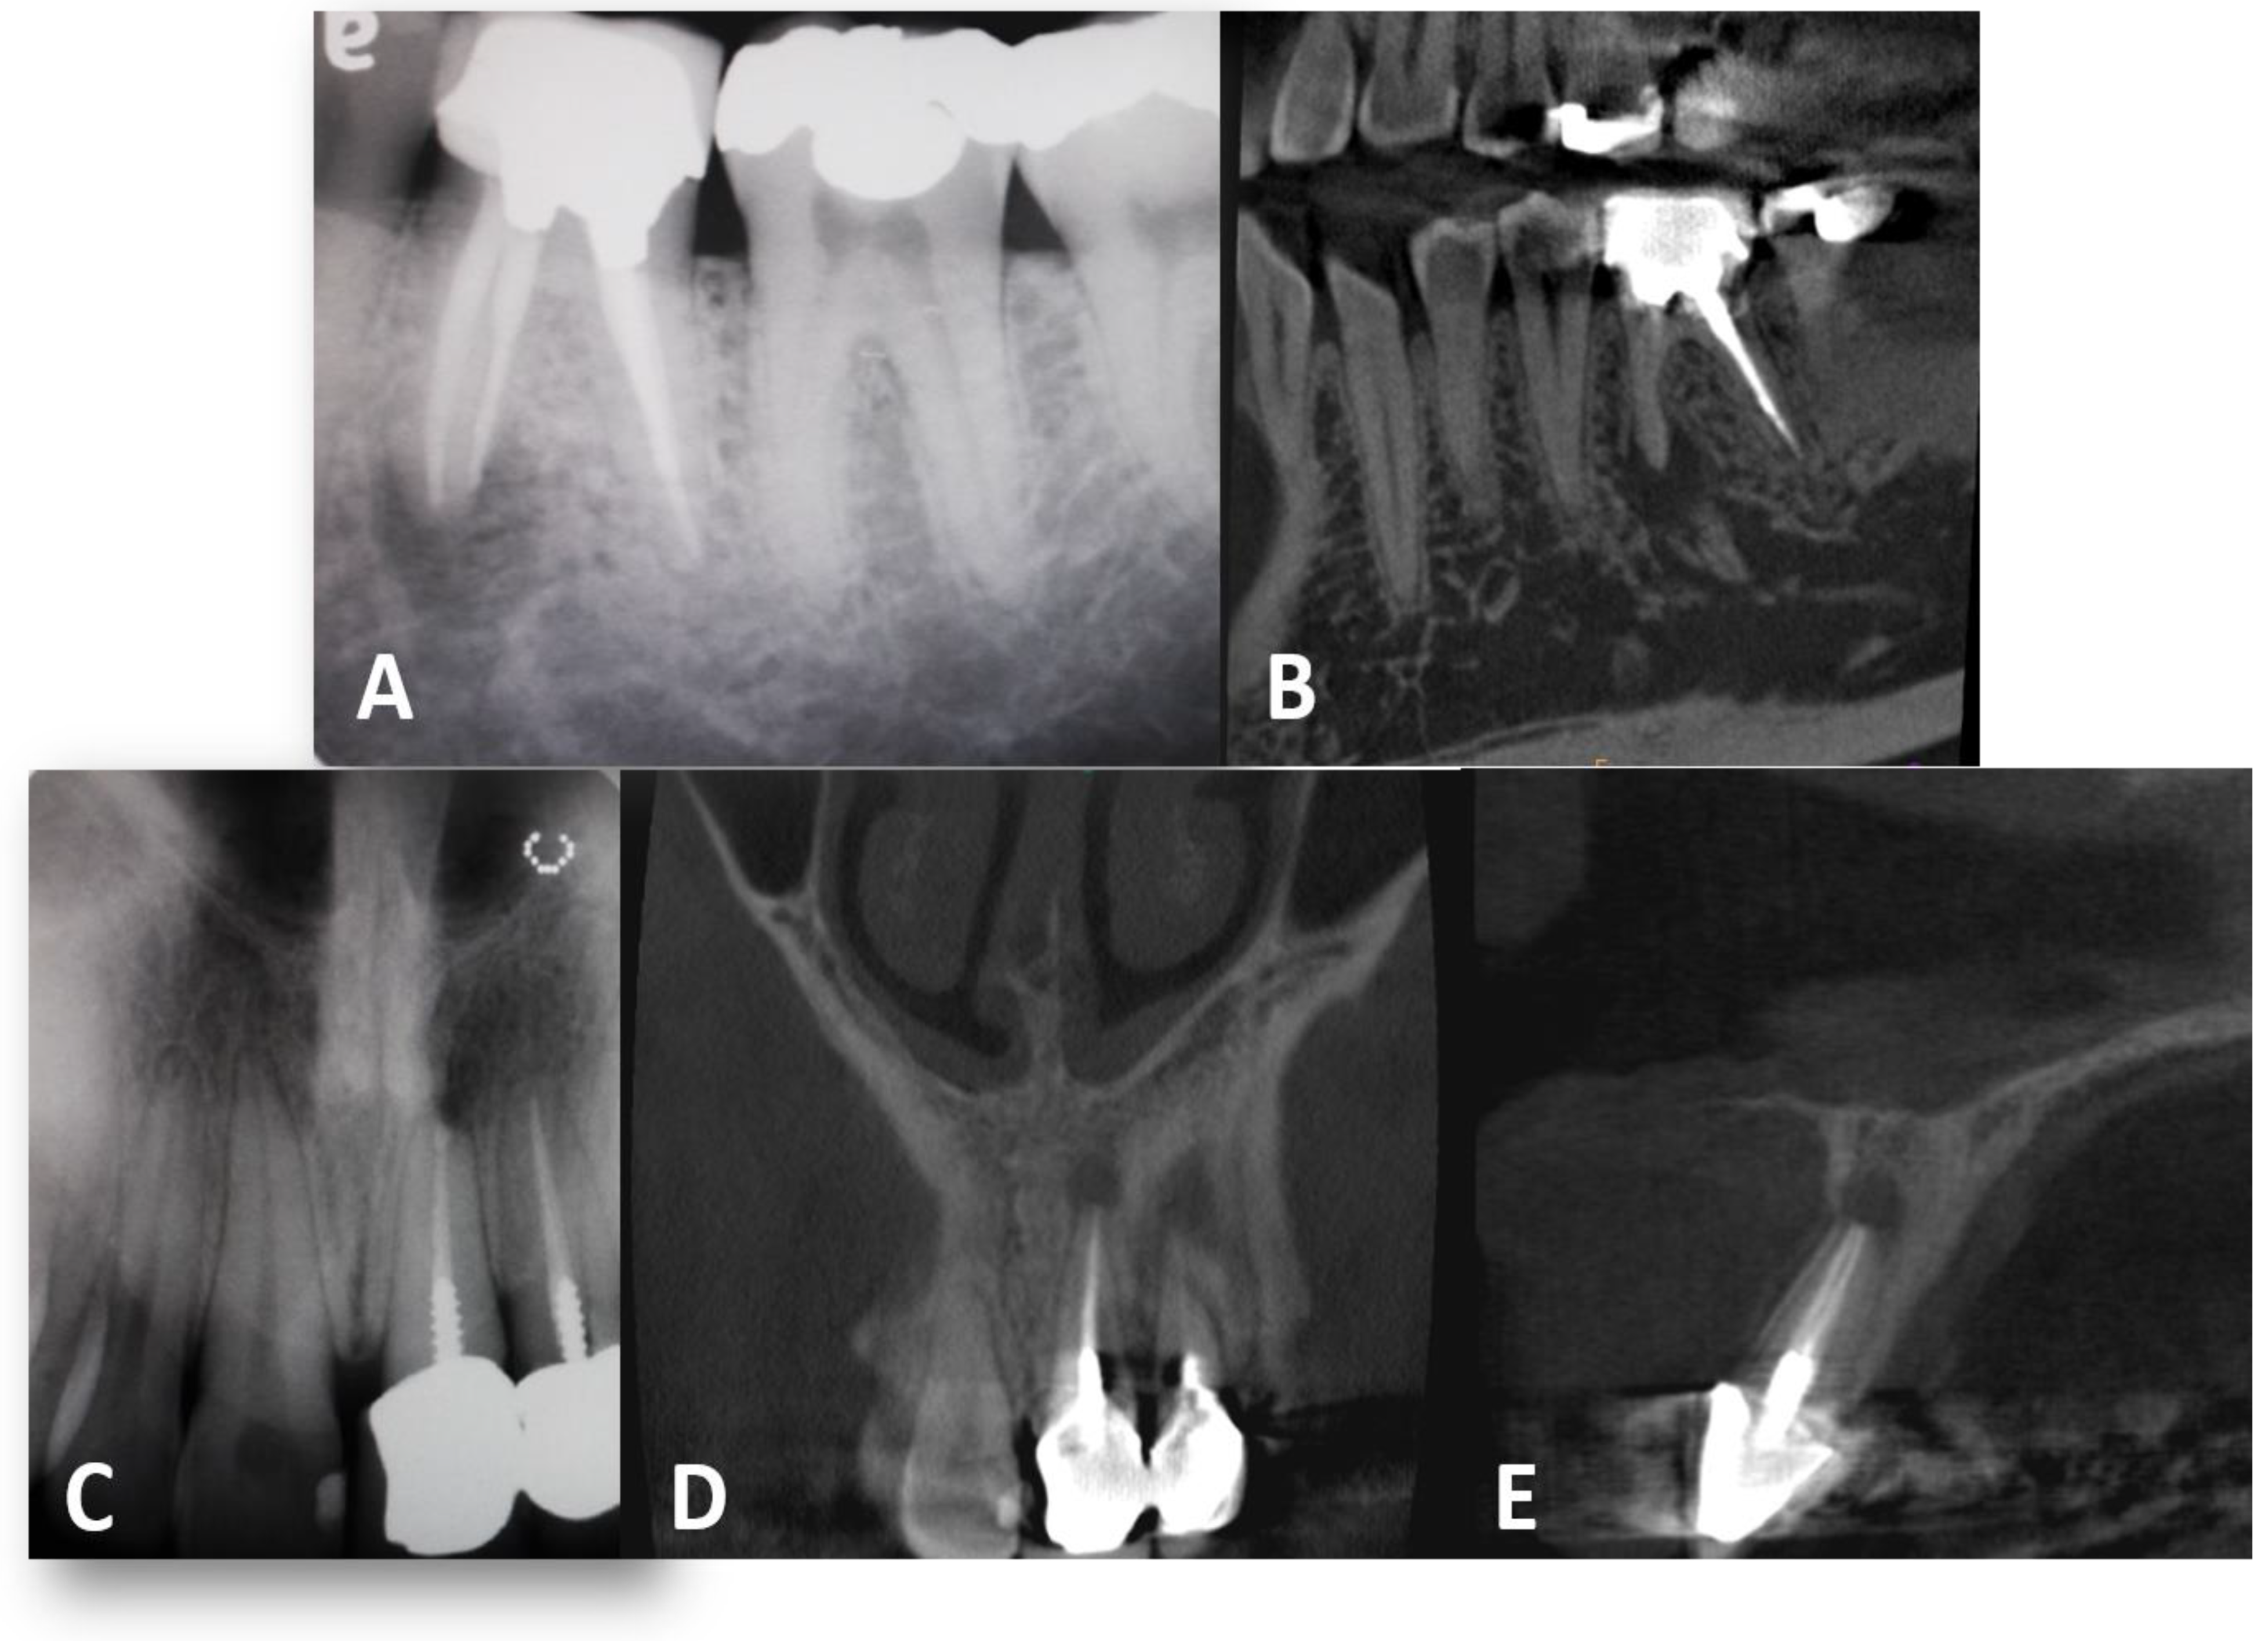

- Teeth with root canal filling, a core without a post

- Teeth with root canal filling, a core with a stainless-steel prefabricated post

- Teeth with root canal filling, cast post and core